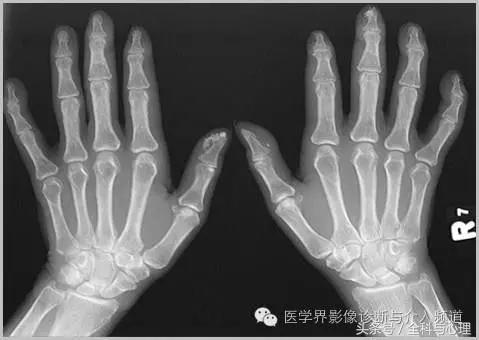

2、 与硬皮病相关的手部局限性钙质沉积

手部皮肤或皮下组织,多发的,边界清晰的,点状、片状的钙化灶,与硬皮病相关。

硬皮病